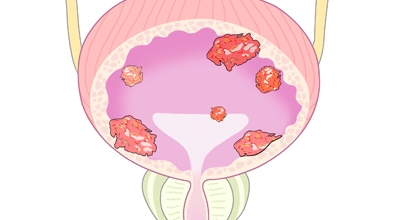

방광암 초기증상

1. 방광암 초기증상 - 하복부 또는 옆구리 통증

방광암에 의해 요관 폐색이 발생할 수 있으며 상피세포에서 발생된 방광암이 방광 전체에 퍼지게 되면 수신증이 생기면서 옆구리 또는 하복부 통증이 발생합니다.

2. 방광암 초기증상 - 부종

통증이나 요관폐색으로 인해 배뇨가 잘 되지 않을 경우 방광암 초기증상으로 부종이 나타날 수 있어요. 하지에 부종이 생기거나, 암이 어느정도 진행된 경우 골반 주변에서 덩어리가 만져지기도 합니다.

3. 방광암 초기증상 - 혈뇨

혈뇨는 소변을 눈으로 확인했을 때 빨갛게 관찰되는 것을 육안적 혈뇨라고 하고 눈으로 보기에는 깨끗하지만 소변검사를 했을 때 혈뇨관 소견으로 관찰되는 현미경적 혈뇨로 구분돼요. 2가지 혈뇨 현상 모두 방광암의 증상으로 볼 수 있으며 이러한 증상이 발생하게 되면 병원의 정밀 검진이 필요합니다. 소변의 색은 붉은색으로 보이기도 하고 녹색으로 보이기도 합니다.

4. 방광암 초기증상 - 배뇨장애 또는 배뇨통

방광암이 생기면 방광의 역할을 제대로 수행하지 못하며 소변을 빈번하게 보는 빈뇨증상이나 갑자기 배뇨를 하는 급 방뇨 현상이 발생합니다. 또 배뇨시 통증이 일어날 수 있어요.

5. 방광암 초기증상 - 식욕감퇴

마지막 방광암 초기증상은 식욕감퇴이지요. 통증이나 무기력함, 피로감 등으로 인해 자연스럽게 식욕이 감소하고 체중의 변화를 느끼기도 합니다.